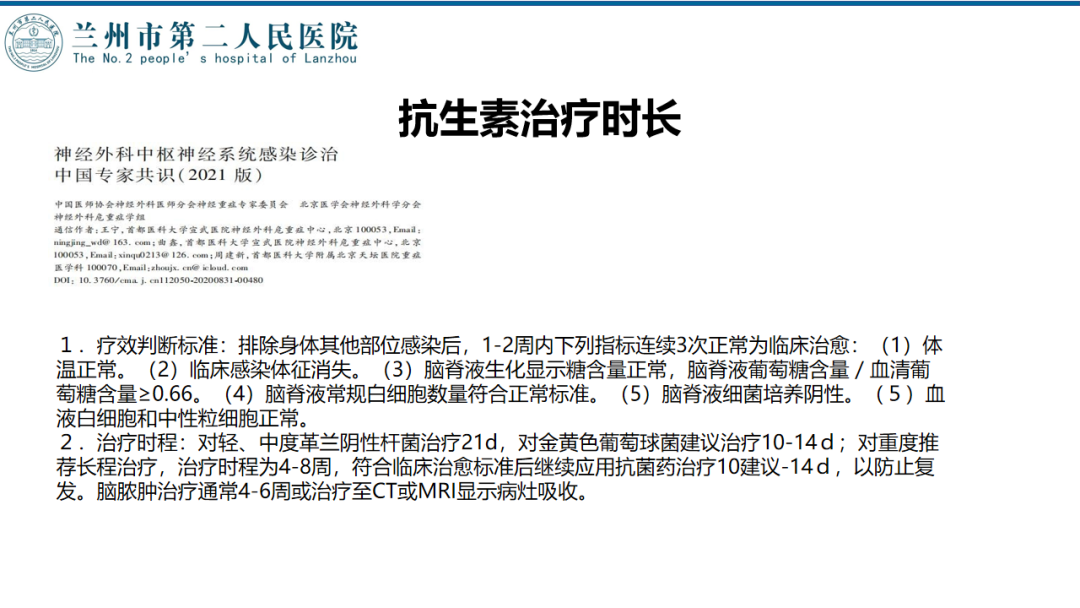

术后随访

术后化验

2周后停抗生素

术后随访

术后72h CT,复查后拔除硬膜下引流管

术后72h胸部 CT

术后1周 CT

术后70天CT